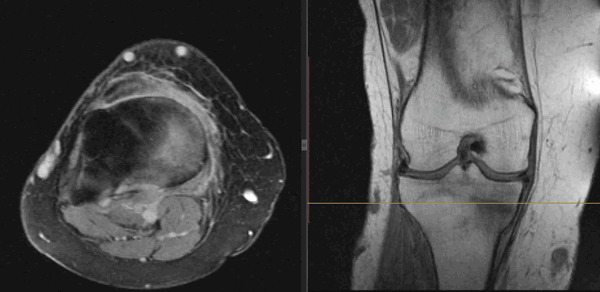

Отдельного внимания заслуживают травмы кисти, стопы. Здесь кости имеют небольшие размеры. Тени их накладываются одна на другую. Оценить состояние костной ткани гораздо точнее можно на трехмерных снимках МРТ и КТ, чем на плоскостных рентгеновских. На МРТ кроме костных нарушений будут видны также сдавление или разрыв нервов, сухожилий, отек, воспаление мышц, суставов.

Изучают на МРТ случаи переломов, если повреждены мягкие ткани, внутрисуставные структуры, долго не проходит симптоматика после травмы несмотря на проводимое лечение. МРТ делают, если планируется оперативное вмешательство, а также для контроля достигнутых результатов лечения. МРТ снимки позволяют создавать трехмерные изображения стопы, колена, поэтому врач может увидеть линии перелома, не заметные на обычной рентгенограмме, изучить состояние каждой косточки.